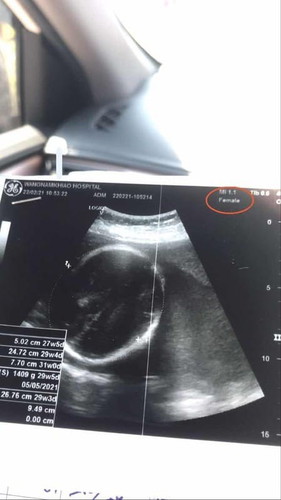

วันนี้ไปโรงบาลมาค่ะ ซาวด์ดูแล้วหมอบอกได้ผู้ชาย แต่ในใบซาวด์ขึ้นว่าfemaleที่แปลว่าผู้หญิง เราสังเกตได้จากตรงไหนคะแม่ๆ

อันนั้นของแม่ค่ะ ไม่ใช่ของลูก